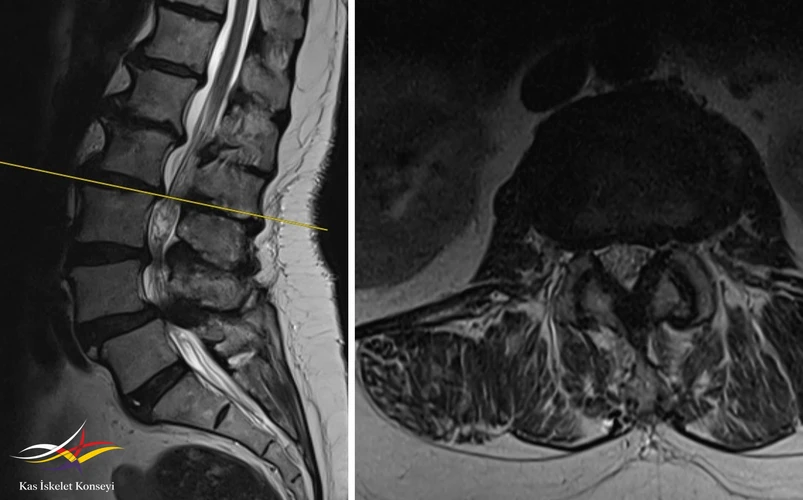

Resim 3. Lomber MRG'de L2-3 seviyesinde ılımlı bir darlık görülmekte.

Resim 4. L3-4 seviyesinde belirgin bir kanal darlığı mevcut.